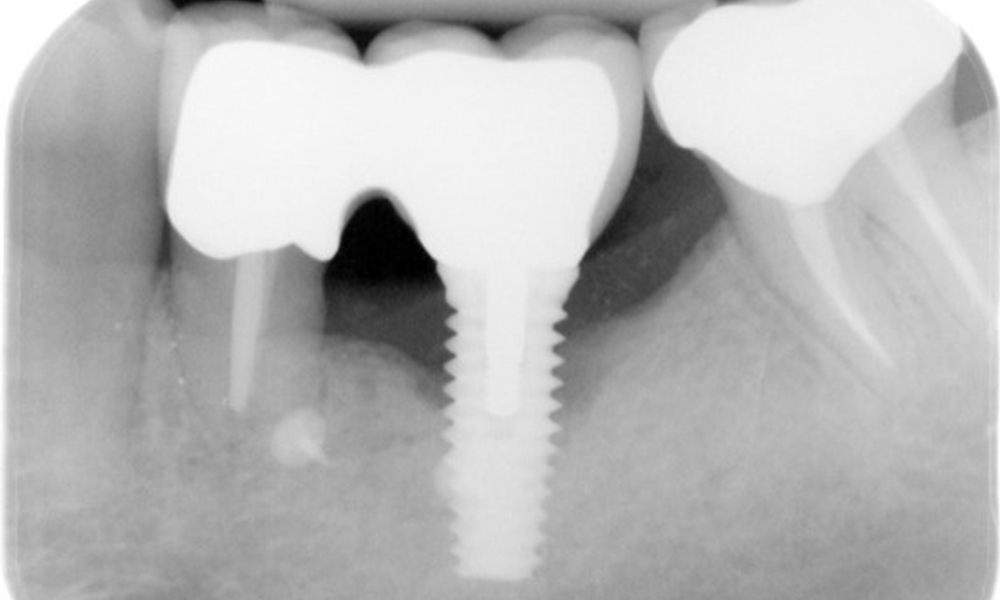

52-годишен пациент се явява на профилактичен преглед. Пациентът няма хронични заболявания и не приема никакви лекарства. Претърпял е различни дентални лечения и също така има две активни кариозни лезии. Освен това има четири импланта (2-ри, 3-ти и 4-ти квадрант). Установява се, че има ранно пародонтално заболяване (стадий IV, степен В). Състоянието на пародонта е стабилно, като дълбочина на сондиране (ST) от 5 mm се проявява само при импланта в област 36. Установен е и гингивит.

В историята на заболяването на пациента няма особени рискови фактори със специфични дентални последици. Следователно ключовият фактор е изискването по отношение на оралното здраве. В това отношение има данни за дълбочина на сондиране от 5 mm при импланта в 3-ти квадрант, а на рентгеновата снимка - за увеличена костна загуба. Пациентът също така има стабилно понастоящем пародонтално заболяване и две активни начални кариозни лезии.